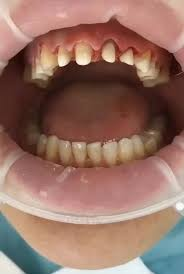

2323.jpg 238Кб, 1412x2047

1412x2047

Аноны, добрый вечер.

Посоветуйте пасту зубную после пломбирования и чистки от камня передних зубов.

Спасибо.